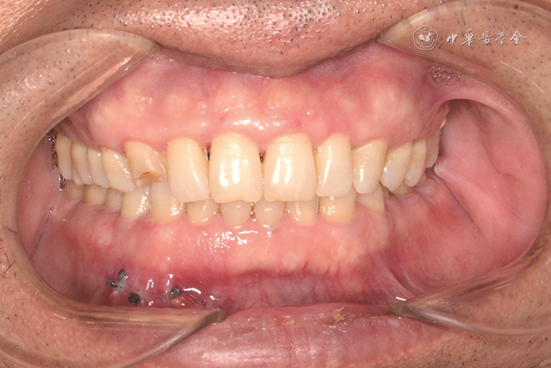

2. 检查:见图1,2。患者右侧面下份和右下颌前庭沟较左侧稍膨隆,表面皮肤无异常;下颌牙列无明显松动;41—43唇侧前庭沟见未愈合切口,缝线在位无松脱,唇侧轻微触压痛,舌侧无明显异常。锥形束CT显示,下颌骨46—32区域大范围不规则骨质破坏区,边界不清,其内密度均匀,牙根无吸收(图2A)。